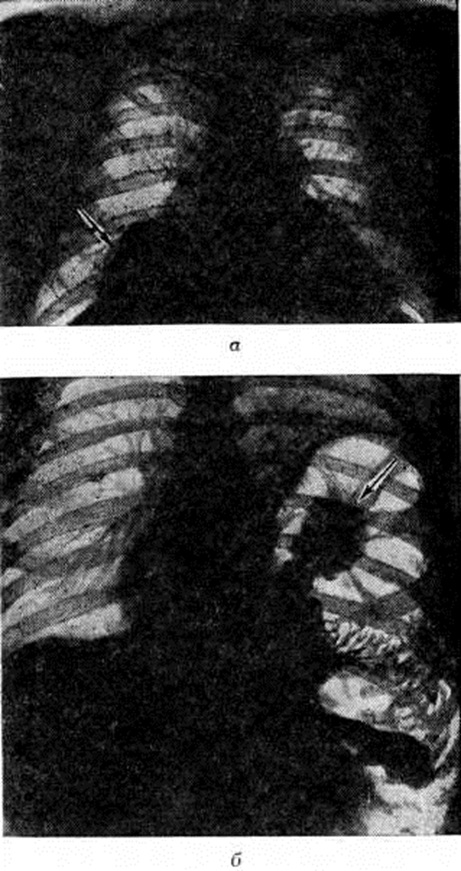

Постановка диагноза Торакоабдоминальные повреждения затруднена. По данным Д. А. Арапова и Н. В. Хорошко (1970), правильный предоперационный диагноз устанавливался у 66,7% раненых с Торакоабдоминальные повреждения Диагностика открытых Торакоабдоминальные повреждения несколько облегчается наличием раневых отверстий, которые иногда могут служить ориентиром для определения хода раневого канала. В этих случаях достоверным признаком Торакоабдоминальные повреждения являются симптомы проникающего ранения груди при локализации раны в области живота и комплекс абдоминальных симптомов при локализации раны в области груди. Еще труднее диагностика закрытых Торакоабдоминальные повреждения Существенную помощь в диагностике оказывают данные рентгенологическое исследования, при котором выявляются признаки пролабирования органов брюшной полости в плевральную полость (рисунок), наличие газа под куполом диафрагмы, ограничение подвижности и высокое стояние диафрагмы и другие